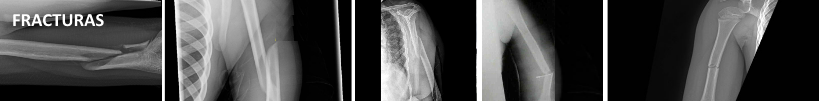

- Fractura, ruptura dun óso despois de sufrir un golpe ou unha caída violentos. Son frecuentes cando se realiza unha actividade deportiva intensa sen un quecemento previo.

Os tipos de fracturas máis comúns suceden a causas de caídas e golpes importantes que terminan por romper o óso.Van acompañadas dunha forte dor na zona e algúns outros síntomas como inflamacións e deformacións , dificultade de movementos, hematomas e moratóns.

Segundo a clasificación as roturas nos ósos poden ser parciais ou totais,(talo verde, sinxela e transversa) dividíndose entre abertas (pódense percibir a primeira ollada, xa que a pel pode mostrar a lesión e mesmo o óso pode traspasar o tecido e saír cara a fóra) e pechadas (o óso non chega a atravesar a pel e a primeira ollada non se pode detectar a rotura,que se verá ao facerse placas).